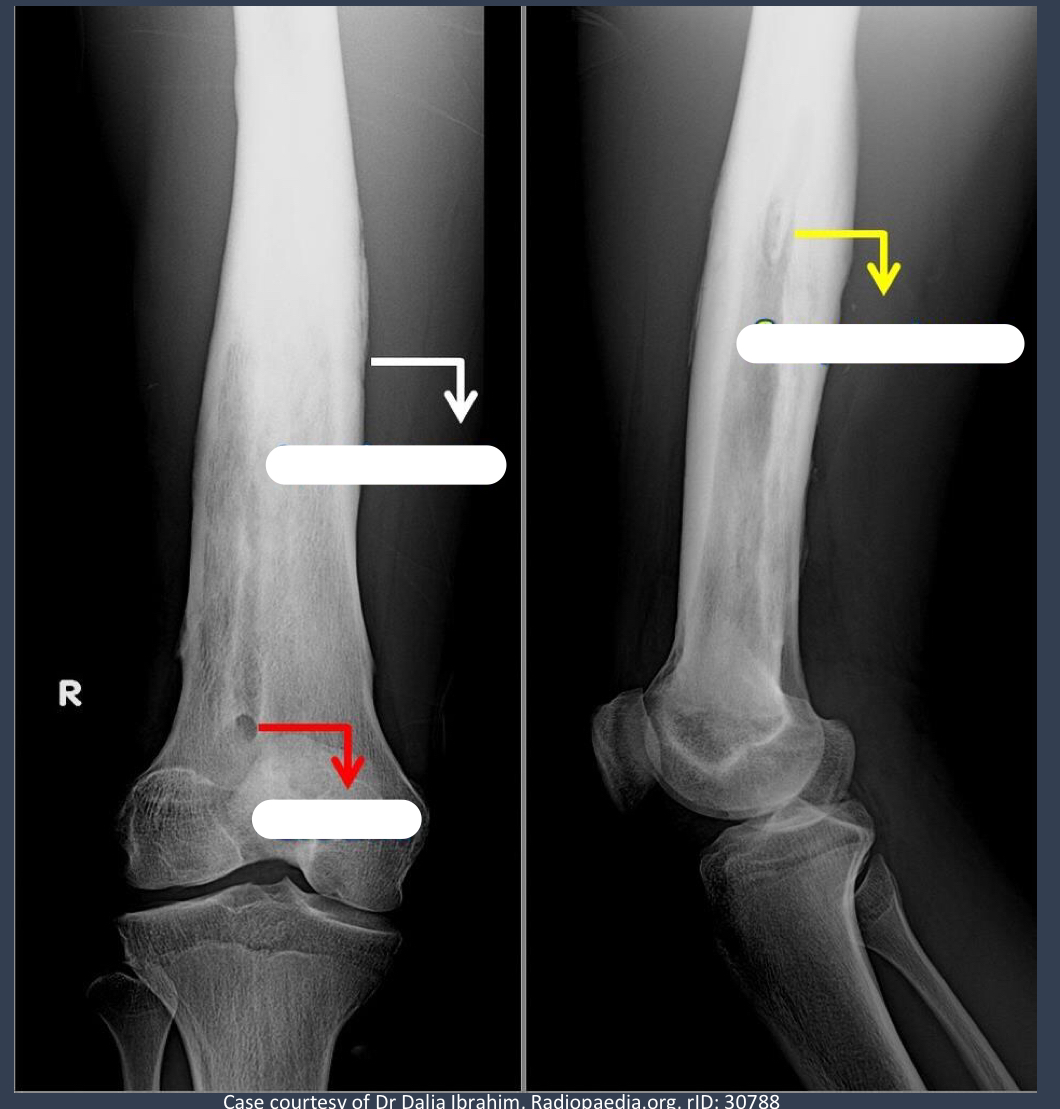

what is noteable in the long bone?

involucrum = thick layer of periosteal new bone that forms around sequestrom

what is the opening from the bone to the skin called that may show up in this patient?

cloaca = opening in an involucrum that drains pus and debris out of infected bone

via sinus tract